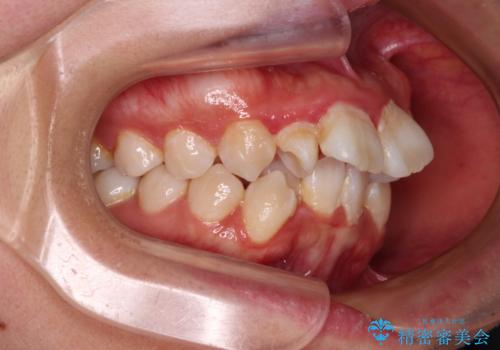

唇からはみ出るほど飛び出した前歯 ワイヤー装置による抜歯矯正

- 飛び出した上顎の前歯と八重歯を気にして来院された患者様です。

口元を積極的に引っ込めるために、上下左右の小臼歯計4本を抜歯することとしました。

下顎前歯の歯肉が元々薄く、歯肉退縮リスクがあったため、細心の注意を払って治療を進めましたが、残念ながら1歯退縮を起こして歯根が露出してしまいました。

今後、患者様と相談しながら、歯肉移植を行っていく予定です。